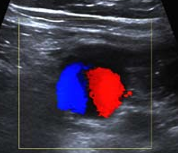

El Doppler ayuda a establecer el diagnóstico, ya que dentro de la lesión quística adyacente al vaso, se observa el signo de Yin Yang: flujo anterógrado y retrógrado en distintos colores, en la porción no trombosada.